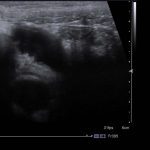

- Surrounding inflammatory changes in the right lower quadrant

Dilated appendix, measuring 9 mm in diameter, which is noncompressible with mild wall thickening and mild mural hyperemia, concerning for acute appendicitis.

Superficial to this is a 2 x 2.5 cm ovoid hypoechoic structure which appears separate from the adjacent bowel and shows no internal vascularity, concerning for a periappendiceal abscess.